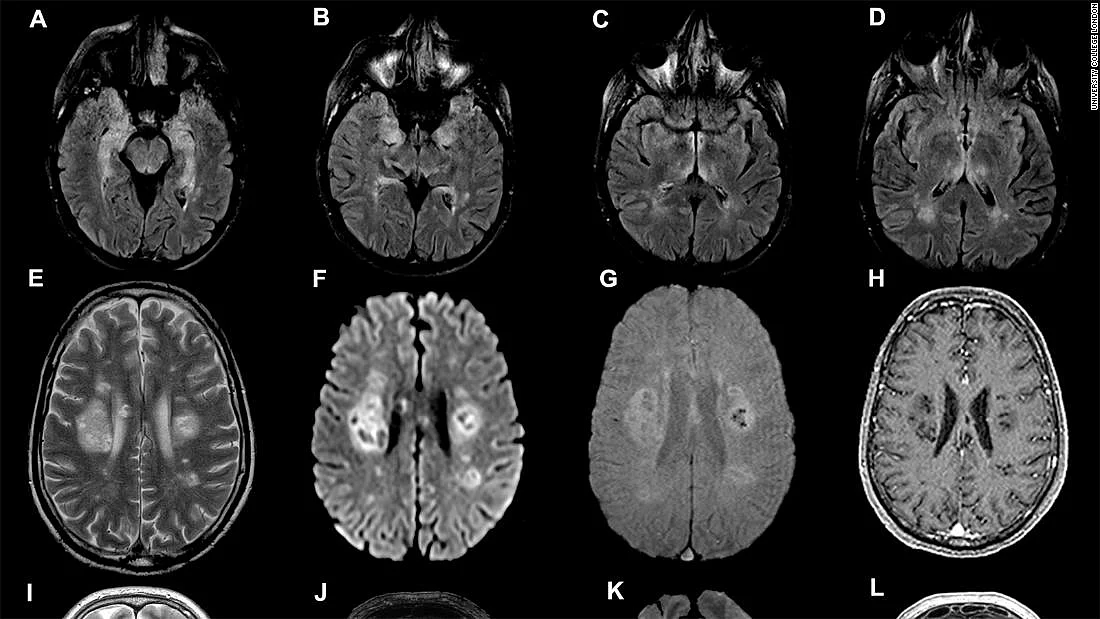

इस अध्ययन के अनुसार, सामान्य इन्फेक्शन की अवस्था में या कोविड 19 के बाद ठीक हुए मरीजों के मस्तिष्क में गंभीर और यहां तक कि जानलेवा बीमारियां भी हो सकती हैं। इस अध्ययन के लिए इंग्लैंड में 40 मरीजों के मस्तिष्क का गहन अध्ययन किया गया। इनके मस्तिष्क में सूजन पाई गई, तंत्रिका तंत्र भी प्रभावित हुआ और कुछ को ब्रेन स्ट्रोक का भी सामना करना पड़ा। अनेक मामलों में मस्तिष्क और तंत्रिका तंत्र की समस्याएं ही अकेली समस्या थी, जिसके कारण या मरीज अस्पताल गए थे और जांच में कोविड 19 का पता चला।

वैज्ञानिकों के अनुसार, इस कोविड 19 के दौर में मस्तिष्क की एक गंभीर समस्या, एक्यूट डिसेमिनेटेड एन्सेफलोमाइलाइटीस, उभर कर सामने आई है और इसके मामले बढ़ते जा रहे हैं। विशेषज्ञों के अनुसार इंग्लैंड के यूनिवर्सिटी कॉलेज ऑफ लन्दन के इंस्टीट्यूट ऑफ न्यूरोलॉजी में इस वैश्विक महामारी के दौर के पहले औसतन महीने में एक मरीज इसका इलाज कराने आता था, पर महामारी के दौर में यह संख्या सप्ताह में तीन मरीज तक पहुंच गई है। यह एक जटिल बीमारी है और जानलेवा भी हो सकती है। एक 59 वर्षीय महिला की इलाज के दौरान मृत्यु हो चुकी है, एक 55 वर्षीय महिला को गंभीर मनोवैज्ञानिक समस्याएं उत्पन्न हो गयीं हैं और तीसरी महिला जिसकी उम्र 47 वर्ष है, उसके मस्तिष्क में भयानक सूजन आ गई है।

कोविड 19 के जिन 40 मरीजों के मस्तिष्क की गहन जांच की गई, उनमें से एक दर्जन से अधिक के सेंट्रल नर्वस सिस्टम में सूजन पाई गई, 10 को मस्तिष्क की बीमारियां हो गई थीं, 8 को ब्रेन स्ट्रोक का सामना करना पड़ा और 8 को पेरिफेरल नर्वस सिस्टम में समस्या उत्पन्न हो गई, जिससे लकवा हो सकता है और 5 प्रतिशत से अधिक मामलों में यह समस्या जानलेवा भी हो सकती है। इस अध्ययन के प्रमुख माइकल जंडी के अनुसार मस्तिष्क पर ऐसा पहले किसी वायरस का प्रभाव नहीं देखा गया। कोविड-19 के बाद ठीक हुए मरीज को सम्भवतः जीवन पर्यंत मस्तिष्क की गंभीर बीमारियों से जूझना पड़ सकता है, जिसमें घातक मल्टीपल स्क्लेरोसिस भी शामिल है।